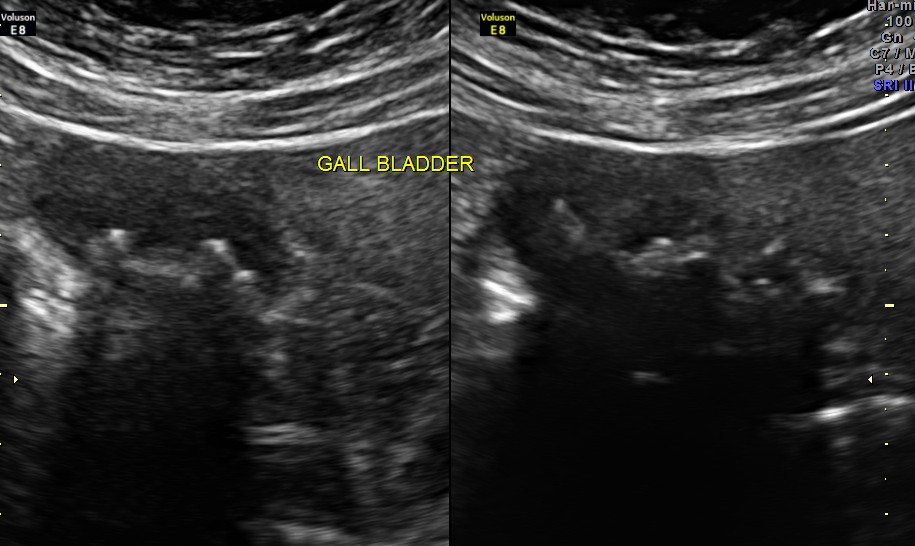

His ultrasound now revealed the following findings :

high definition live reconstruction shows the echodensities in the posterior wall of the gallbladder